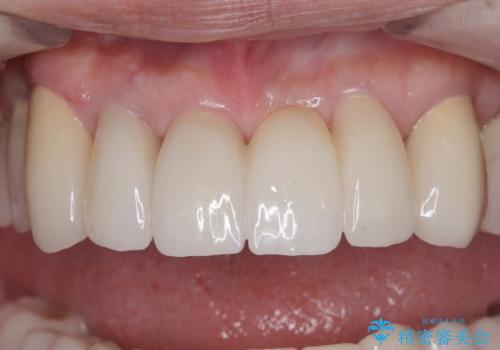

上顎口蓋からの堅い歯肉を移植する角化歯肉移植術を行いたかったのですが、体調不良から実施しなかったため、最終補綴物であるオールセラミッククラウンを装着した後に、知覚過敏や境目が見てしまうといった問題が一部で発生いたしました。

最終的には痛みや違和感のない状態にて治療を終えることができました。